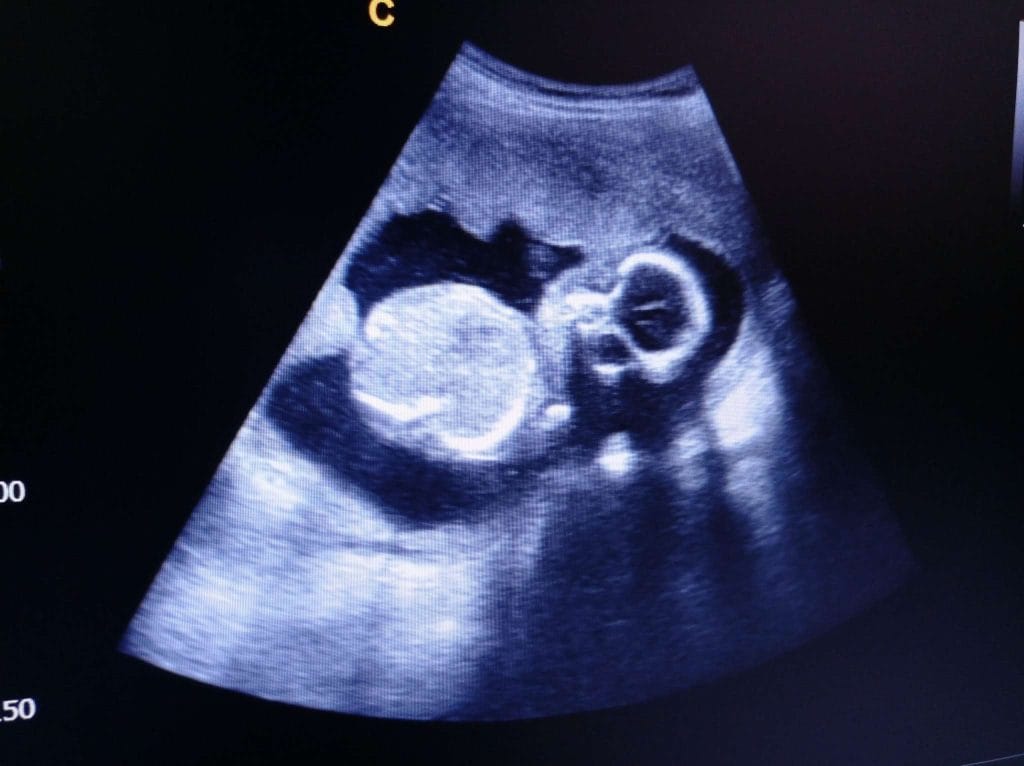

Ultrason Görüntülerinde 19. Hafta

Gebeliğin 19. haftasında ultrason muayenesi, hem bebeğin gelişimini değerlendirmek hem de olası anomalileri tespit etmek açısından kritik bir öneme sahiptir. Bu dönem, genellikle ayrıntılı ikinci trimester ultrasonu (detaylı ultrason veya anomali taraması) için uygun zamandır.

Ultrasonda bebeğin tüm organ sistemleri detaylı bir şekilde incelenir. Beyin, kalp, böbrekler, mide, bağırsaklar ve omurga gibi hayati yapılar ayrıntılı olarak değerlendirilir. Ayrıca bebeğin kemikleri, kolları ve bacakları ölçülerek gelişim haftaya uygun mu diye kontrol edilir.

- hafta ultrasonunda görülebilecek en önemli bulgulardan biri de bebeğin cinsiyetidir. Bebeğin pozisyonuna bağlı olarak cinsiyet net bir şekilde ayırt edilebilir. Ancak kesin sonuç için doktorun değerlendirmesi esastır.

Bu haftada yapılan detaylı ultrason, bebeğin gelişiminde herhangi bir yapısal problem olup olmadığını ortaya koymada en güvenilir yöntemlerden biridir. Ayrıca plasentanın konumu ve amniyon sıvısının miktarı da doktor tarafından dikkatle incelenir.

Anne adayları için 19. hafta ultrasonu oldukça heyecan verici bir deneyimdir. Bebeğin parmağını emdiği, esnediği veya hareket ettiği anlar ultrason ekranında net bir şekilde izlenebilir. Bu görüntüler hem anne hem baba için gebelik sürecini daha somut ve özel kılar.